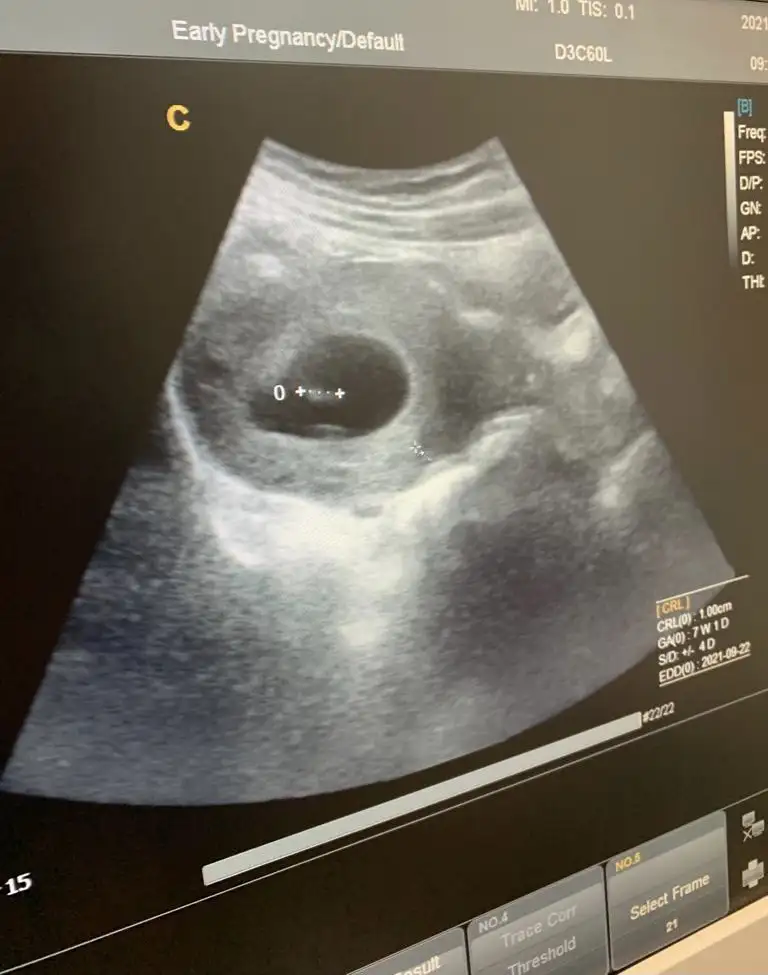

Ya minnağa bak sennn mașallahEki Görüntüle 2775874

Kızlar çok şükür bebişi gördük ve kalp atışını duydukHepimizin bebişleri sağlıklı sıhhatli gelişip doğsunlar inşallah B bitkiselhayat canım sence cinsiyeti ne başka bilen arkadaşlarda yorumlarsa sevinirim Benim bi fikrim var ama bakalım bilemiyorum

Nasipse eylül annesi olucam ben de..herkes sağ salim kucağına alsın inşallah bebeklerini

Bin yüz milyon kere maşallah Canım ya rabbim sağlıcakla kucağına almayı da nasip etsin inşallahEki Görüntüle 2775874